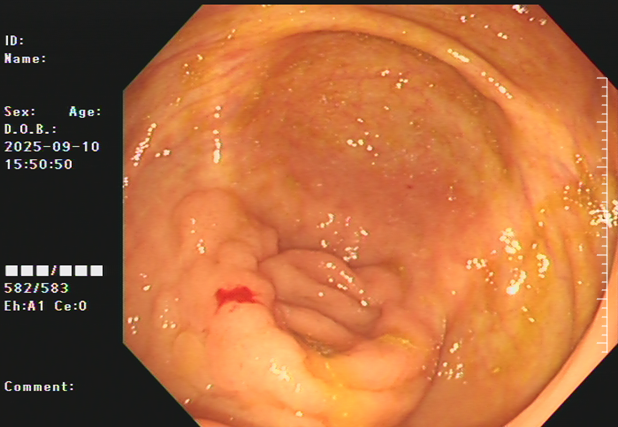

吴姨(化名)平素饮食规则,无腹痛、便血等消化道不适,因其侄女有大肠肿瘤病史,为求安心,特从外地来连州市人民医院进行肠镜检查。消化内镜室吕美光医生在检查中,凭借丰富经验和高清放大染色内镜技术,于盲肠深处发现一个与正常黏膜极其相似、范围达35mmX45mm的平坦微隆起型病灶,并确认其微表面及微血管结构存在异型。后续活检证实,该病灶为盲肠管状腺瘤。